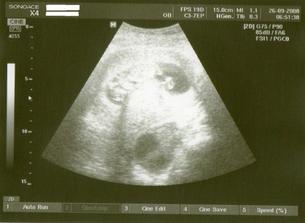

Tak jsme po UTZ,miminko se mlelo a krásně hýbalo,vše bylo vidět,vše je v pořádku a hlavně

JE TO KLUK....TAKŽE BUDEME MÍT MATYÁŠKA🙂))))))